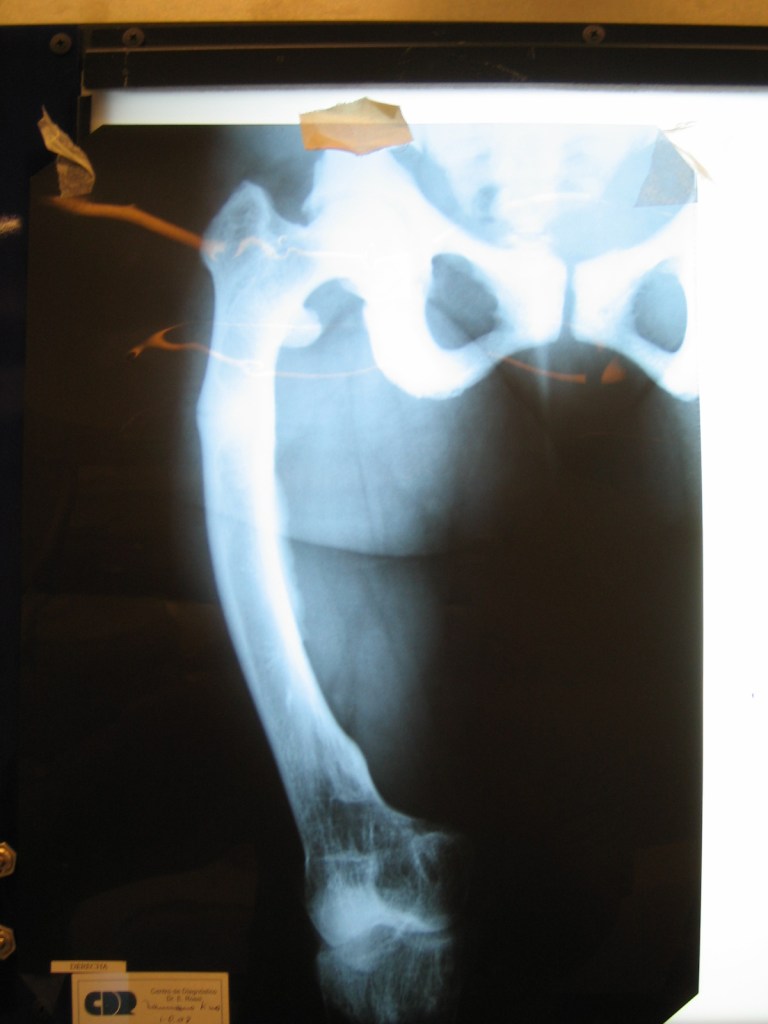

Lina namuncura

raquitismo congenito

Mensaje de Agradecimiento

Pese a tomar la medicacion indicada desde pequeña, mis huesos se deformaron tanto por mi raquitismo que me impedian caminar y solo podia trasladarme en silla de ruedas.tras varias consultas en diferentes centros del pais donde me decian que no podia hacerse nada llegue a Cotram.

fue en ese momento y tras una consulta de mas de una hora donde me explicaron paso a paso las cirugias necesarias para lograr lo que yo queria

luego de un año de tratamientos y cirugías logre enderezar todos mis huesos